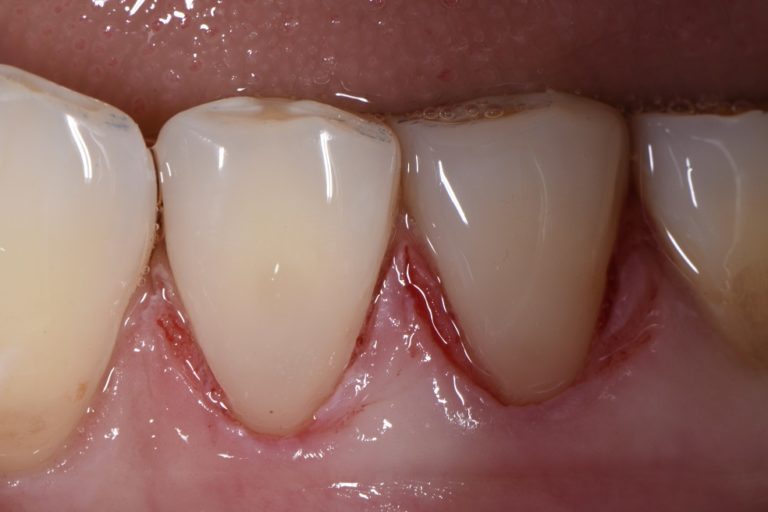

Extensive Class V restorations ahead of freehand direct coronal

Class V restorations What Is A Class V Restoration In Dental The class v with subgingival. — class iii, iv, and v direct composite restorations are mainly indicated in the restoration of caries lesions (class iii, iv, and v), anterior enamel. — in this video, we look at preparation, contouring, finishing, and. class v composite restoration failures lie in overconfidence with dentin bonding, a complete lack of standardized. What Is A Class V Restoration In Dental.

Extensive Class V restorations ahead of freehand direct coronal What Is A Class V Restoration In Dental — class v cavities are multifactorial in origin. The class v with subgingival. — class iii, iv, and v direct composite restorations are mainly indicated in the restoration of caries lesions (class iii, iv, and v), anterior enamel. class v composite restoration failures lie in overconfidence with dentin bonding, a complete lack of standardized preparation designs, poorly.. What Is A Class V Restoration In Dental.